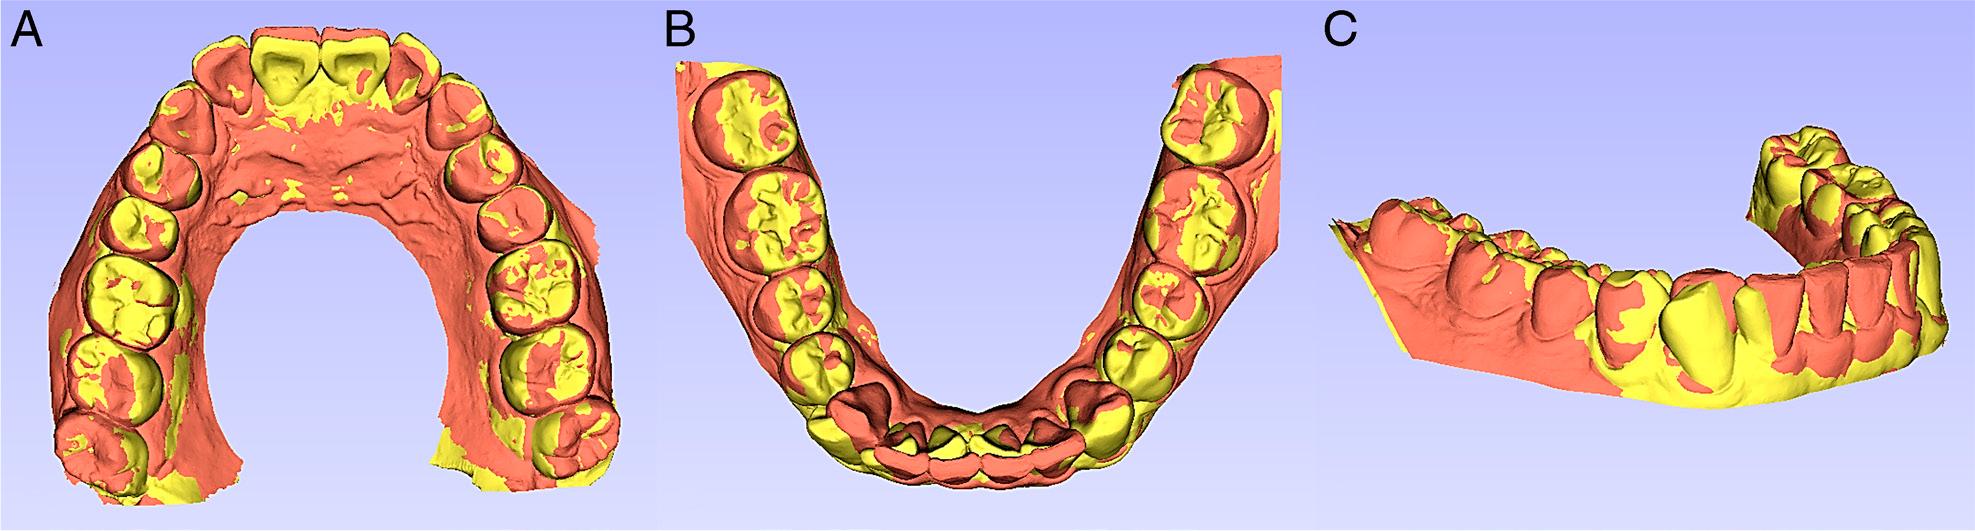

Model superimposition. The yellow colour denotes the pre-treatment model, and the orange colour represents the post-treatment model. The registrations were performed on the occlusal surfaces of the first and second molars. A, Maxillary dentition. B, Mandibular dentition. C, Oblique view.

The panoramic radiograph showed the distal movement of the right mandibular canine root (Figure 11). The post-treatment cephalometric measurements and superimposition of the pre- and the post-treatment films demonstrated that incisal proclination occurred without compromising the facial profile (Figure 11, Table I).